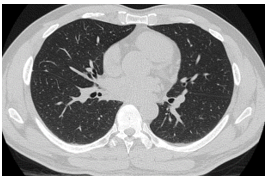

Hình 2: Hình ảnh chọc sinh thiết tổn thương vùng phổi phải dưới hướng dẫn chụp cắt lớp vi tính lồng ngực